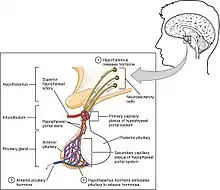

Hypothalamic control

Hormone secretion from the anterior pituitary gland is regulated by hormones secreted by the hypothalamus. Neuroendocrine cells in the hypothalamus project axons to the median eminence, at the base of the brain. At this site, these cells can release substances into small blood vessels that travel directly to the anterior pituitary gland (the hypothalamo-hypophyseal portal vessels).

Other mechanisms

Aside from hypothalamic control of the anterior pituitary, other systems in the body have been shown to regulate the anterior pituitary's function. GABA can either stimulate or inhibit the secretion of luteinizing hormone (LH) and growth hormone (GH) and can stimulate the secretion of thyroid-stimulating hormone (TSH). Prostaglandins are now known to inhibit adrenocorticotropic hormone (ACTH) and also to stimulate TSH, GH and LH release.[9] Clinical evidence supports the experimental findings of the excitatory and inhibitory effects GABA has on GH secretion, dependent on GABA's site of action within the hypothalamic-pituitary axis.[10]